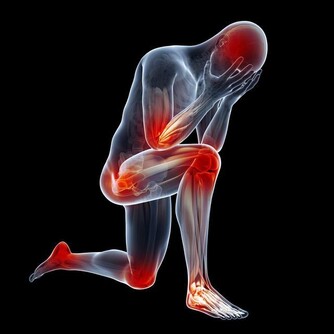

正常情況下,人體每天生成與排出的尿酸保持著平衡。尿酸升高有兩個方面的因素:一是產生的多,二是排泄的少。

此外,正常情況下,約有2/3 的血尿酸通過腎臟排出人體。

當患腎臟疾病導致腎臟功能下降時,尿酸會慢慢在體內堆積,同樣可使血尿酸濃度上升,導致痛風。